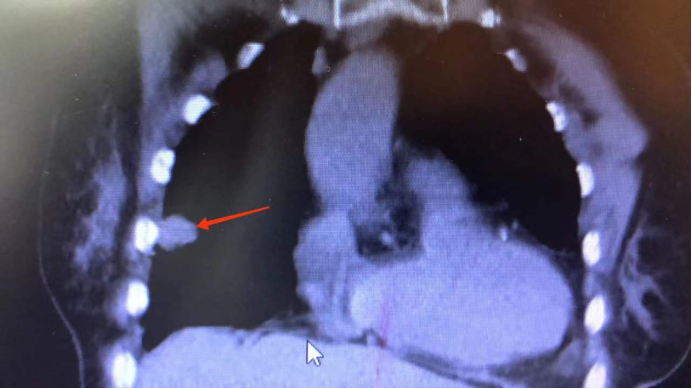

入院胸部CT示:双肺及双侧胸膜多发结节、团片影,考虑肿瘤可能;纵隔及双肺门淋巴结显示,部分增大。患者肺部多发占位性质不明,需肺活检明确病变,但患者年龄大,平素身体状况差,经我科医师团队讨论及沟通后,准备通过一种方法简单,费用低廉,无辐射的活检技术---超声引导下经皮肺穿刺活检术来明确诊断。5月12日,在呼吸与危重症医学科郑艾波医生和超声医学科姚辉鸿医师的精心配合和细心操作下,成功完成手术并明确了诊断。

CT显示病灶